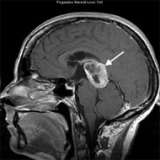

An MRI scan shows a large tumor (arrow) in the pineal region of the brain. The biopsy confirmed glioblastoma, which is rare in this part of the brain. This illustrates the importance of obtaining a tissue biopsy in most cases.

- A magnetic resonance imaging (MRI) of the brain is the most important imaging study. It will show the location, size and shape of the tumor.